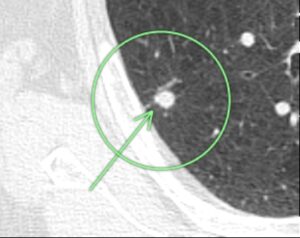

(症例1)82歳 女性

胸部CTで左上葉、○枠、矢印の部位に10㎜大の結節(すりガラス型)を認めました。

9年後の胸部CTにおいても、大きさに変化は認められません。

この所見は癌ではなく前癌状態と考えられ、積極的な手術の適応はなく、引き続き経過観察を行っています。